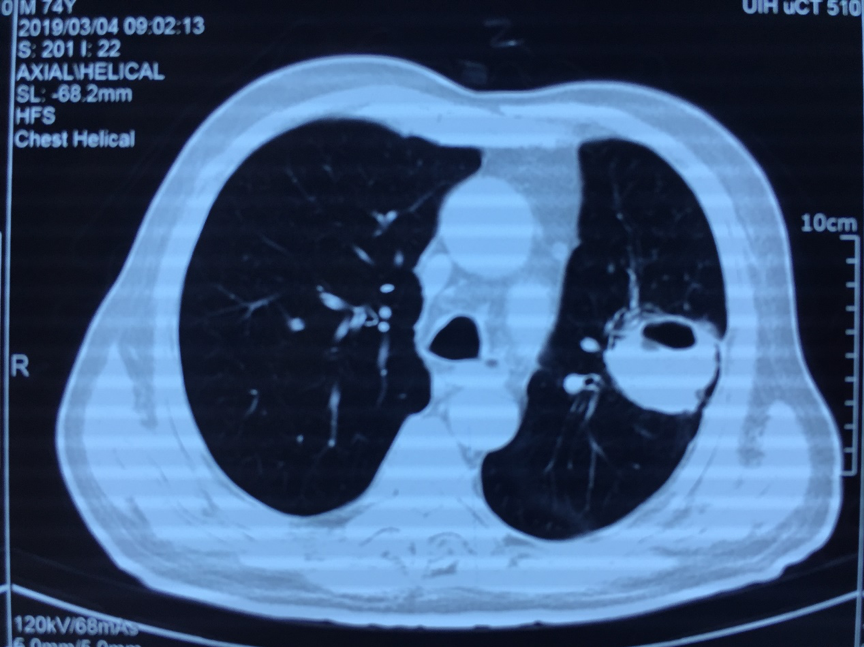

74 岁老年男性,主因「咳嗽、咳痰、腰痛 1 月」入院。患者 1 月前受凉后出现发热,伴咳嗽,咳大量黄痰,同时伴有腰骶部疼痛,向双下肢放射,伴双下肢麻木感。就诊于某骨科专科医院,行腰椎 MRI 检查提示「腰 1-3 水平椎管内及腰骶部,双侧腰大肌、竖脊肌内多发异常强化」(图 1-2),胸部 CT 提示左上肺类圆形厚壁空洞影,偏心性空洞。(图 3)。痰细菌培养为「肺炎链球菌」。行 B 超引导下腰椎旁脓肿穿刺,抽出脓性液体,培养为「肺炎链球菌」。予美罗培南抗感染,并行腰椎感染清创+VSD 引流术。术后患者体温正常,但仍感咳嗽咳痰。复查胸部 CT(图 4)左肺空洞较前无明显变化。患者既往高血压、糖尿病病史。

图 3 胸部 CT(2019-3-4)左肺上叶偏心型空洞

图 4 胸部 CT(2019-3-20)抗感染治疗 2 周后,复查仍可见左肺偏心性空洞,较前吸收不明显。

当不能单纯用肺炎链球菌感染解释的临床现象(肺内病灶规范抗感染吸收不明显,同时出现椎旁及肺内多处病灶等)时,应该回到起点思考。肺炎链球菌是常见引起肺炎的病原体。当患者长期吸烟、糖尿病控制不佳等情况时,会有进一步侵入形成肺脓肿或坏死性肺炎可能。重新阅读患者胸部 CT 可见,左肺团块有分叶,团块周围胸膜侵犯,空洞为偏心型,肿瘤标记物正常,该患者长期吸烟史,肺癌可能性不能除外。因此积极建议患者选择有创检查获取标本,进行病理检查。